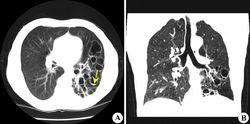

先天性支氣管源性囊腫常見於兒童病例,囊腫位於肺間質或縱隔內。約70%位於肺內,30%位於縱隔。由於囊腫可為單個或多個,含氣體或液體量不同,因而在X線胸片上可呈現不同表現:

1.單個液氣囊腫:最為常見,囊腫大小不一,可見圓形薄壁囊腫,內有液面。此種囊腫的特點是囊壁菲薄,鄰近肺組織無炎性浸潤病變,纖維性變不多,需與肺膿腫,肺結核空洞和肺包蟲囊腫鑑別。在X線上表現肺膿腫壁較厚,周圍炎症表現明顯,肺結核空洞則有較長病史,周圍有結核衛星灶。肺包蟲囊腫有流行病學的地區特點、生活史和職業史、血像、皮內試驗等有助於鑑別。

2.單個氣囊腫:胸片上示病側肺部含氣囊腫,巨大的氣囊腫可占據一側胸腔,壓迫肺,氣管,縱隔,心臟,需與氣胸鑑別。氣胸的特點是肺萎縮推向肺門,而氣囊腫的空氣位於肺內,往往仔細觀察在肺尖和肋隔角處可見到肺組織。

3.多個氣囊腫:臨床也較多見,胸片上呈現多個大小不一、邊緣不齊的氣囊腫,需與多個肺大皰鑑別。尤其在小兒,肺大皰常伴有肺炎,在X線上以透亮圓形薄壁大皰及其大小、數目、形態的易變性為特徵。每在短期隨訪中就見較多變化,有時可迅速增大,或破裂後形成氣胸。肺部炎症一旦消退,大皰有時可自行縮小或消失。

4.多發性液、氣囊腫:胸片上可見多個大小不一的液、氣腔。尤其病變位於左側者,需與先天性膈疝鑑別,後者也可呈現為多個液平,必要時口服碘油或稀鋇檢查,若在胸腔內見到造影劑進入胃腸道,則為隔疝。